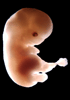

Carnegie Stage 20 (50 post-ovulatory days)

Most embryos at stage 20 are approximately 50-51 postovulatory days old and measure 21-23 mm in length. Distinguishing criteria for this stage include upper limbs slightly bent at the elbows, short stubby fingers, hands curving over the cardiac region but still far apart from each other, and a fringe-like vascular plexus that marks growth centers laterally in the superficial tissues of the head.

Although some of the photographs below show abnormal embryos, the animations and MRI slice images all depict normal embryos. Abnormal embryos are noted in the titles of the large photos when they are opened.